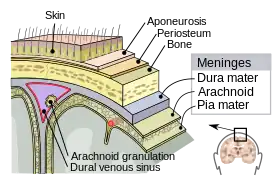

A skull fracture is a break in one or more of the eight bones that form the cranial portion of the skull, usually occurring as a result of blunt force trauma. If the force of the impact is excessive, the bone may fracture at or near the site of the impact and cause damage to the underlying structures within the skull such as the membranes, blood vessels, and brain.

A fracture in conjunction with an overlying laceration that tears the epidermis and the meninges, or runs through the paranasal sinuses and the middle ear structures, bringing the outside environment into contact with the cranial cavity is called a compound fracture. Compound fractures can either be clean or contaminated.

Anatomy

The human skull is anatomically divided into two parts: the neurocranium, formed by eight cranial bones that houses and protect the brain—and the facial skeleton (viscerocranium) composed of fourteen bones, not including the three ossicles of the inner ear.[22] The term skull fracture typically means fractures to the neurocranium, while fractures of the facial portion of the skull are facial fractures, or if the jaw is fractured, a mandibular fracture.[23]

The eight cranial bones are separated by sutures : one frontal bone, two parietal bones, two temporal bones, one occipital bone, one sphenoid bone, and one ethmoid bone.[24]

The bones of the skull are in three layers: the hard compact layer of the external table (lamina externa), the diploë (a spongy layer of red bone marrow in the middle, and the compact layer of the inner table (Lamina interna).[25]

Skull thickness is variable, depending on location. Thus the traumatic impact required to cause a fracture depends on the impact site. The skull is thick at the glabella, the external occipital protuberance, the mastoid processes, and the external angular process of the frontal bone. Areas of the skull that are covered with muscle have no underlying diploë formation between the internal and external lamina, which results in thin bone more susceptible to fractures.

Skull fractures occur more easily at the thin squamous temporal and parietal bones, the sphenoid sinus, the foramen magnum (the opening at the base of the skull that the spinal cord passes through), the petrous temporal ridge, and the inner portions of the sphenoid wings at the base of the skull. The middle cranial fossa, a depression at the base of the cranial cavity forms the thinnest part of the skull and is thus the weakest part. This area of the cranial floor is weakened further by the presence of multiple foramina; as a result this section is at higher risk for basilar skull fractures to occur. Other areas more susceptible to fractures are the cribriform plate, the roof of orbits in the anterior cranial fossa, and the areas between the mastoid and dural sinuses in the posterior cranial fossa.[26]